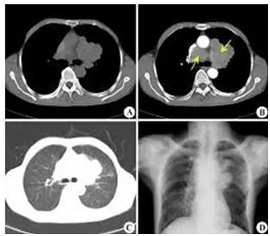

尽管影像学检查被认为是评价肺癌治疗效果的金标准,但是影像学对追踪微小残留病灶(MRD)不能准确及时反映,并且通过形态学改变评价疗效具有滞后的特点,不能在早期反应肿瘤治疗效果13。

肺癌影像学征象